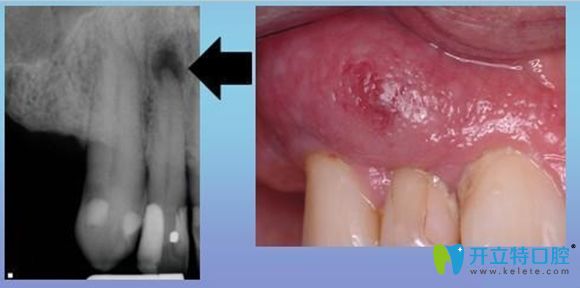

牙齦瘺管癥狀示意圖

牙齦瘺管它是一種常見的口腔疾病,其形成的原因很多,但是主要原因多是根尖周炎引起的。

它的臨床癥狀多表現(xiàn)為,患牙根部位置會(huì)先出現(xiàn)一個(gè)腫包,然后這個(gè)包會(huì)逐漸變大,并伴隨著分泌物溢出。

是因?yàn)榧毙愿庵苎装Y形成膿腫,膿液引流不暢,往外排出導(dǎo)致的,也可以說是根尖周炎癥常見的一種排膿途徑。